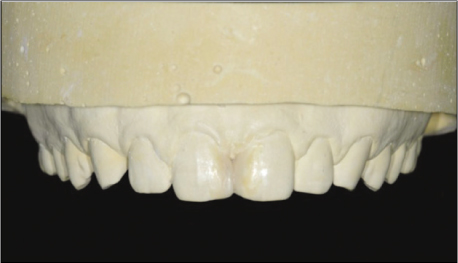

Figure 3The dental cast was waxed up to establish the shape of the restoration.

Figure 2b). Based on the distance, the contact point was defined approximately 5.0 mm from the bone crest. The study model was mocked up so that a plan of proposed esthetic treatment could be presented to the patient. The analysis of the length and the width of the upper central incisors demonstrated an unfavorable proportion after the closure with composite resin (

Figure 3). But, the patient was satisfied with the result of the study model. Therefore, the closure using direct composite resin was decided.